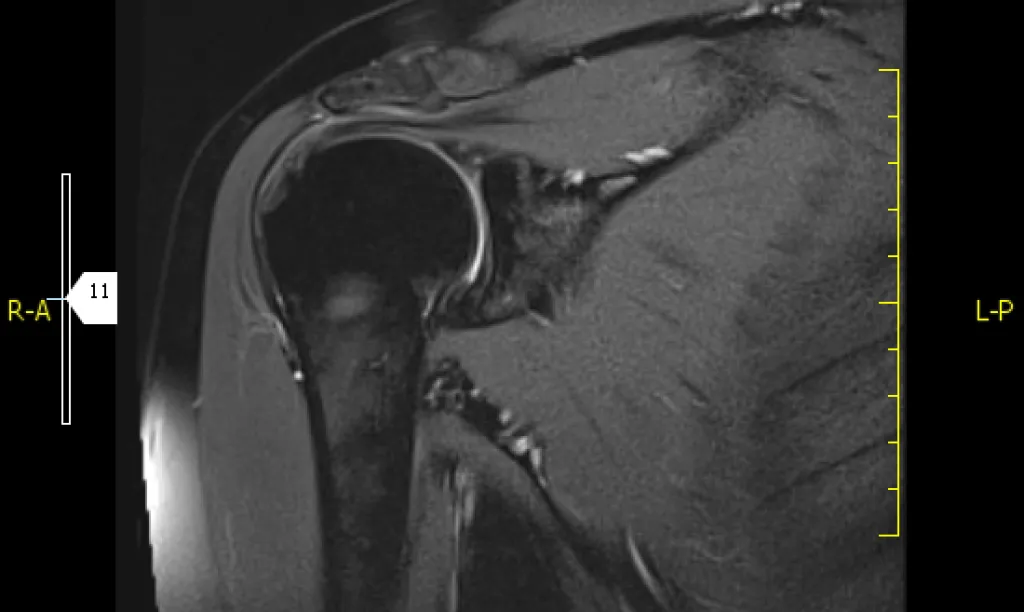

La resonancia magnética es una prueba irremplazable en la valoración de ciertas áreas anatómicas como el musculoesquelético (rodillas, hombro, caderas…) y neurológicos (columna, cerebral,…).

La resonancia magnética es una técnica diagnóstica no invasiva e indolora que se basa en la acción del campo magnético de determinada fuerza y ondas de radio que estimulan los átomos de hidrógeno de los tejidos que conforman nuestro cuerpo. Al desexcitarse, los tejidos emiten una señal que reciben unas antenas y que transforma dicha energía en imágenes.

Se realizan distintas secuencias para obtener imágenes en distintos planos y así poder valorar correctamente todas estructuras desde todos los ángulos.